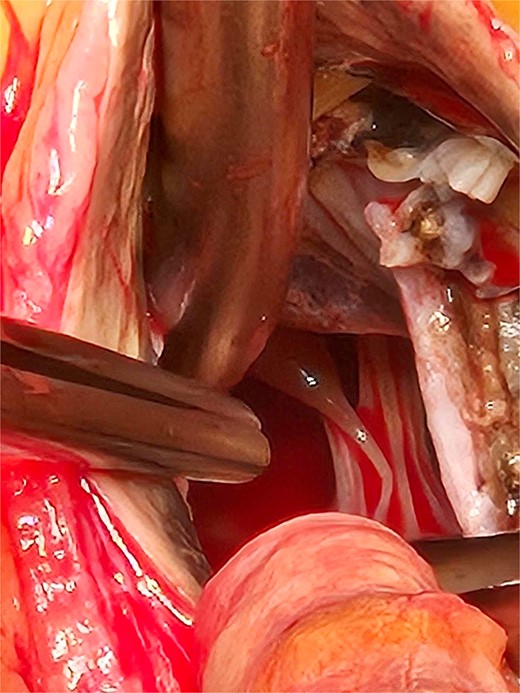

Based on these findings, the patient underwent surgical aortic biological valve replacement and coronary artery bypass grafting (CABG) using a left internal mammary artery graft to the LAD. Intraoperatively, unexpected ochronotic pigmentation was observed in the aortic and mitral valve leaflets, papillary muscles, and the intimal layer of the aortic root, presenting as patchy black discoloration (Figs 1–3). Subsequent biochemical analysis confirmed elevated homogentisic acid levels in the urine, consistent with alkaptonuria.

The extent of the ochronotic uptake can be seen extending to the level of the papillary muscles.